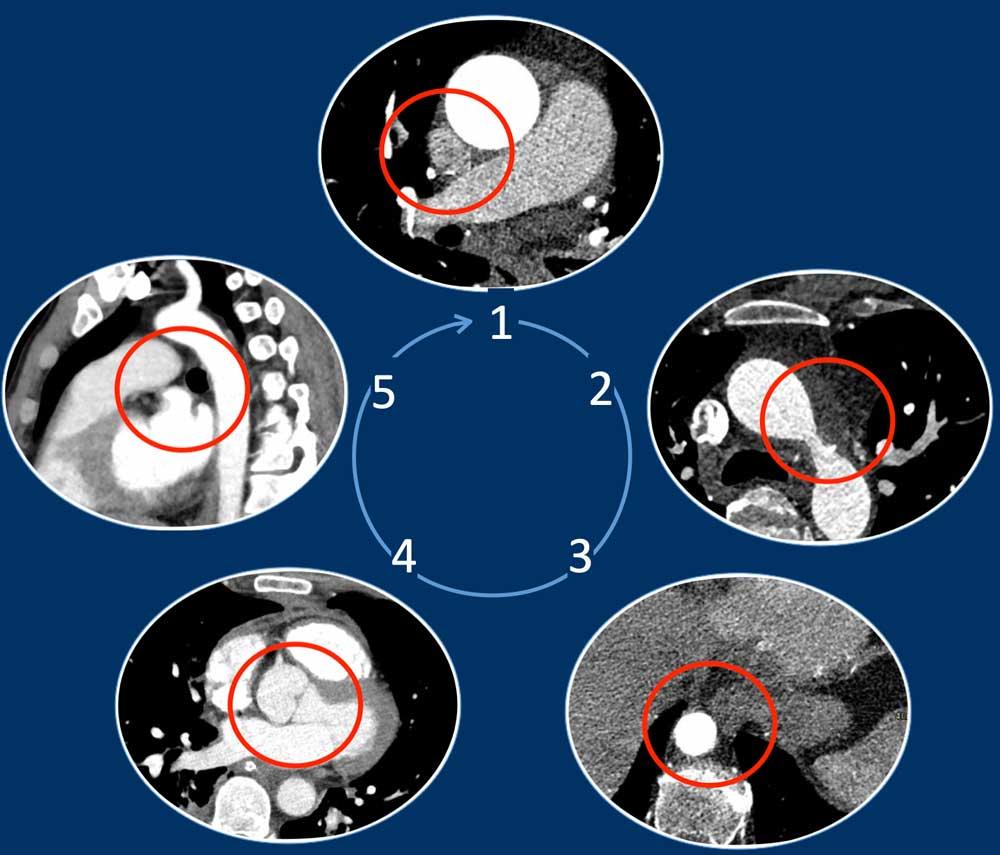

Phương pháp Năm Góc

Phát hiện các bất thường mạch máu trên phim CT ngực không chụp tim có thể là một thách thức, đặc biệt khi chúng không được nghi ngờ trước và do đó không phải là trọng tâm chính của cuộc khảo sát.

Chỉ cần kiểm tra năm góc, có thể phát hiện được phần lớn các biến thể mạch máu:

- Giao điểm giữa tĩnh mạch phổi trên phải và tĩnh mạch chủ trên (mặt cắt ngang)

Chẩn đoán phân biệt: Bất thường hồi lưu tĩnh mạch phổi bán phần (PAPVR) bên phải. - Phía bên ngoài cung động mạch chủ (mặt cắt ngang)

Chẩn đoán phân biệt: Tĩnh mạch chủ bên trái, tĩnh mạch hồng y nhĩ trái, PAPVR bên trái, tĩnh mạch liên sườn trên bên trái. - Động mạch chủ xuống ở mức cơ hoành (mặt cắt ngang)

Chẩn đoán phân biệt: Cấp máu động mạch hệ thống cho phổi, tiếp nối tĩnh mạch đơn thay thế tĩnh mạch chủ dưới, tĩnh mạch Scimitar. - Mức gốc động mạch chủ (mặt cắt ngang)

Chẩn đoán phân biệt: Bất thường nguyên ủy động mạch vành. - Cửa sổ phế động mạch (mặt cắt đứng dọc)

Chẩn đoán phân biệt: Còn ống động mạch, túi thừa động mạch chủ, động mạch dưới đòn phải bất thường.